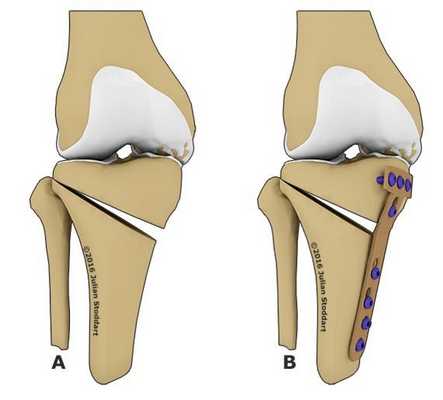

Остеотомия коленного сустава: визуальное изображение процедуры.